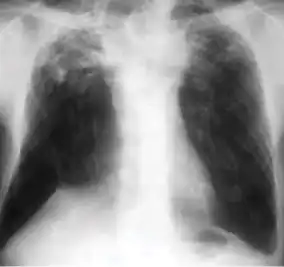

In active pulmonary TB, infiltrates or consolidations and/or cavities are often seen in the upper lungs with or without mediastinal or hilar lymphadenopathy.[1] However, lesions may appear anywhere in the lungs. In HIV and other immunosuppressed persons, any abnormality may indicate TB or the chest X-ray may even appear entirely normal.[1]

Dense homogenous opacity in right, middle and lower lobe of primary pulmonary TB. -

Chest x-ray showing patchy opacification on the upper right and mid-zone lung with fibrotic shadows, as well as bilateral hilar lymphadenopathy. -